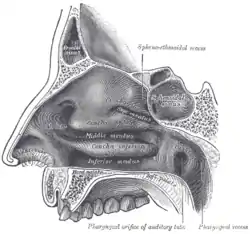

Soft palate without tonsils (after tonsillectomy) Sagittal section of nose mouth, pharynx, and larynx.

The mouth cavity. The cheeks have been slit transversely and the tongue pulled forward. Lateral wall of nasal cavity. (Soft palate visible in lower right)

Lateral wall of nasal cavity. (Soft palate visible in lower right)